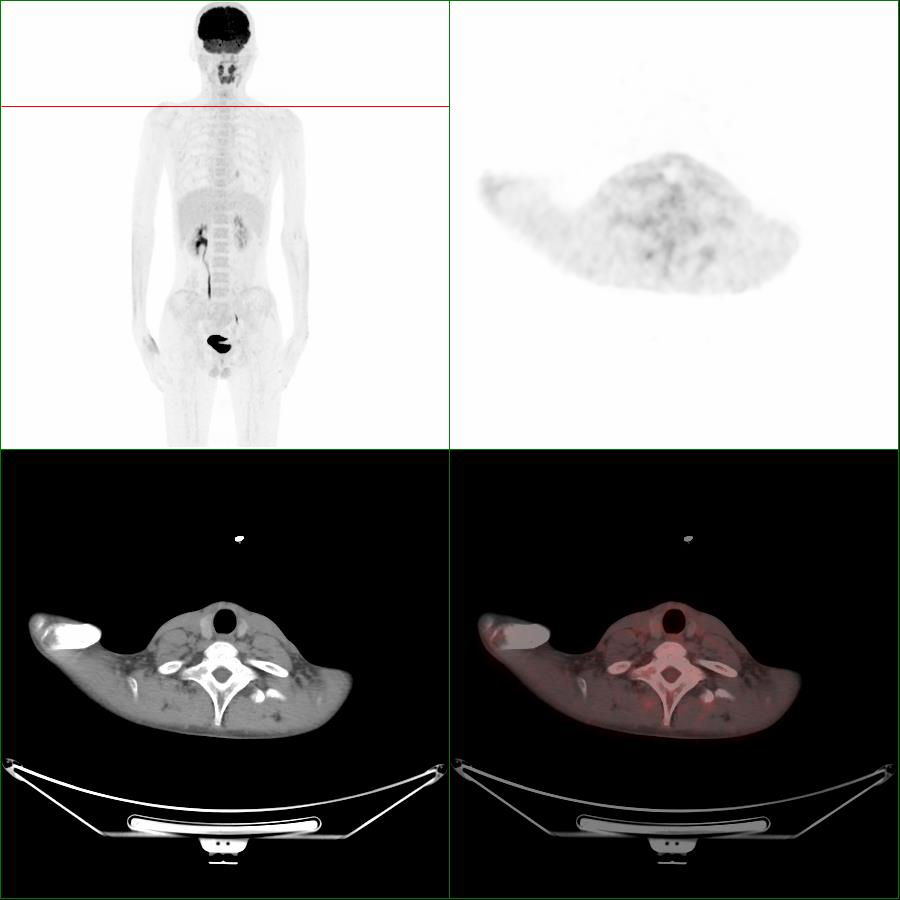

圖2 同一患者3天后第2次顯像